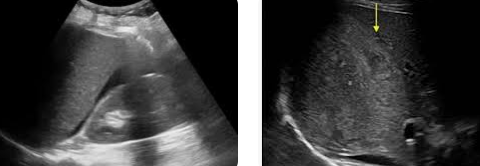

trauma

subcapsular hematoma

intraparenchymal hematoma